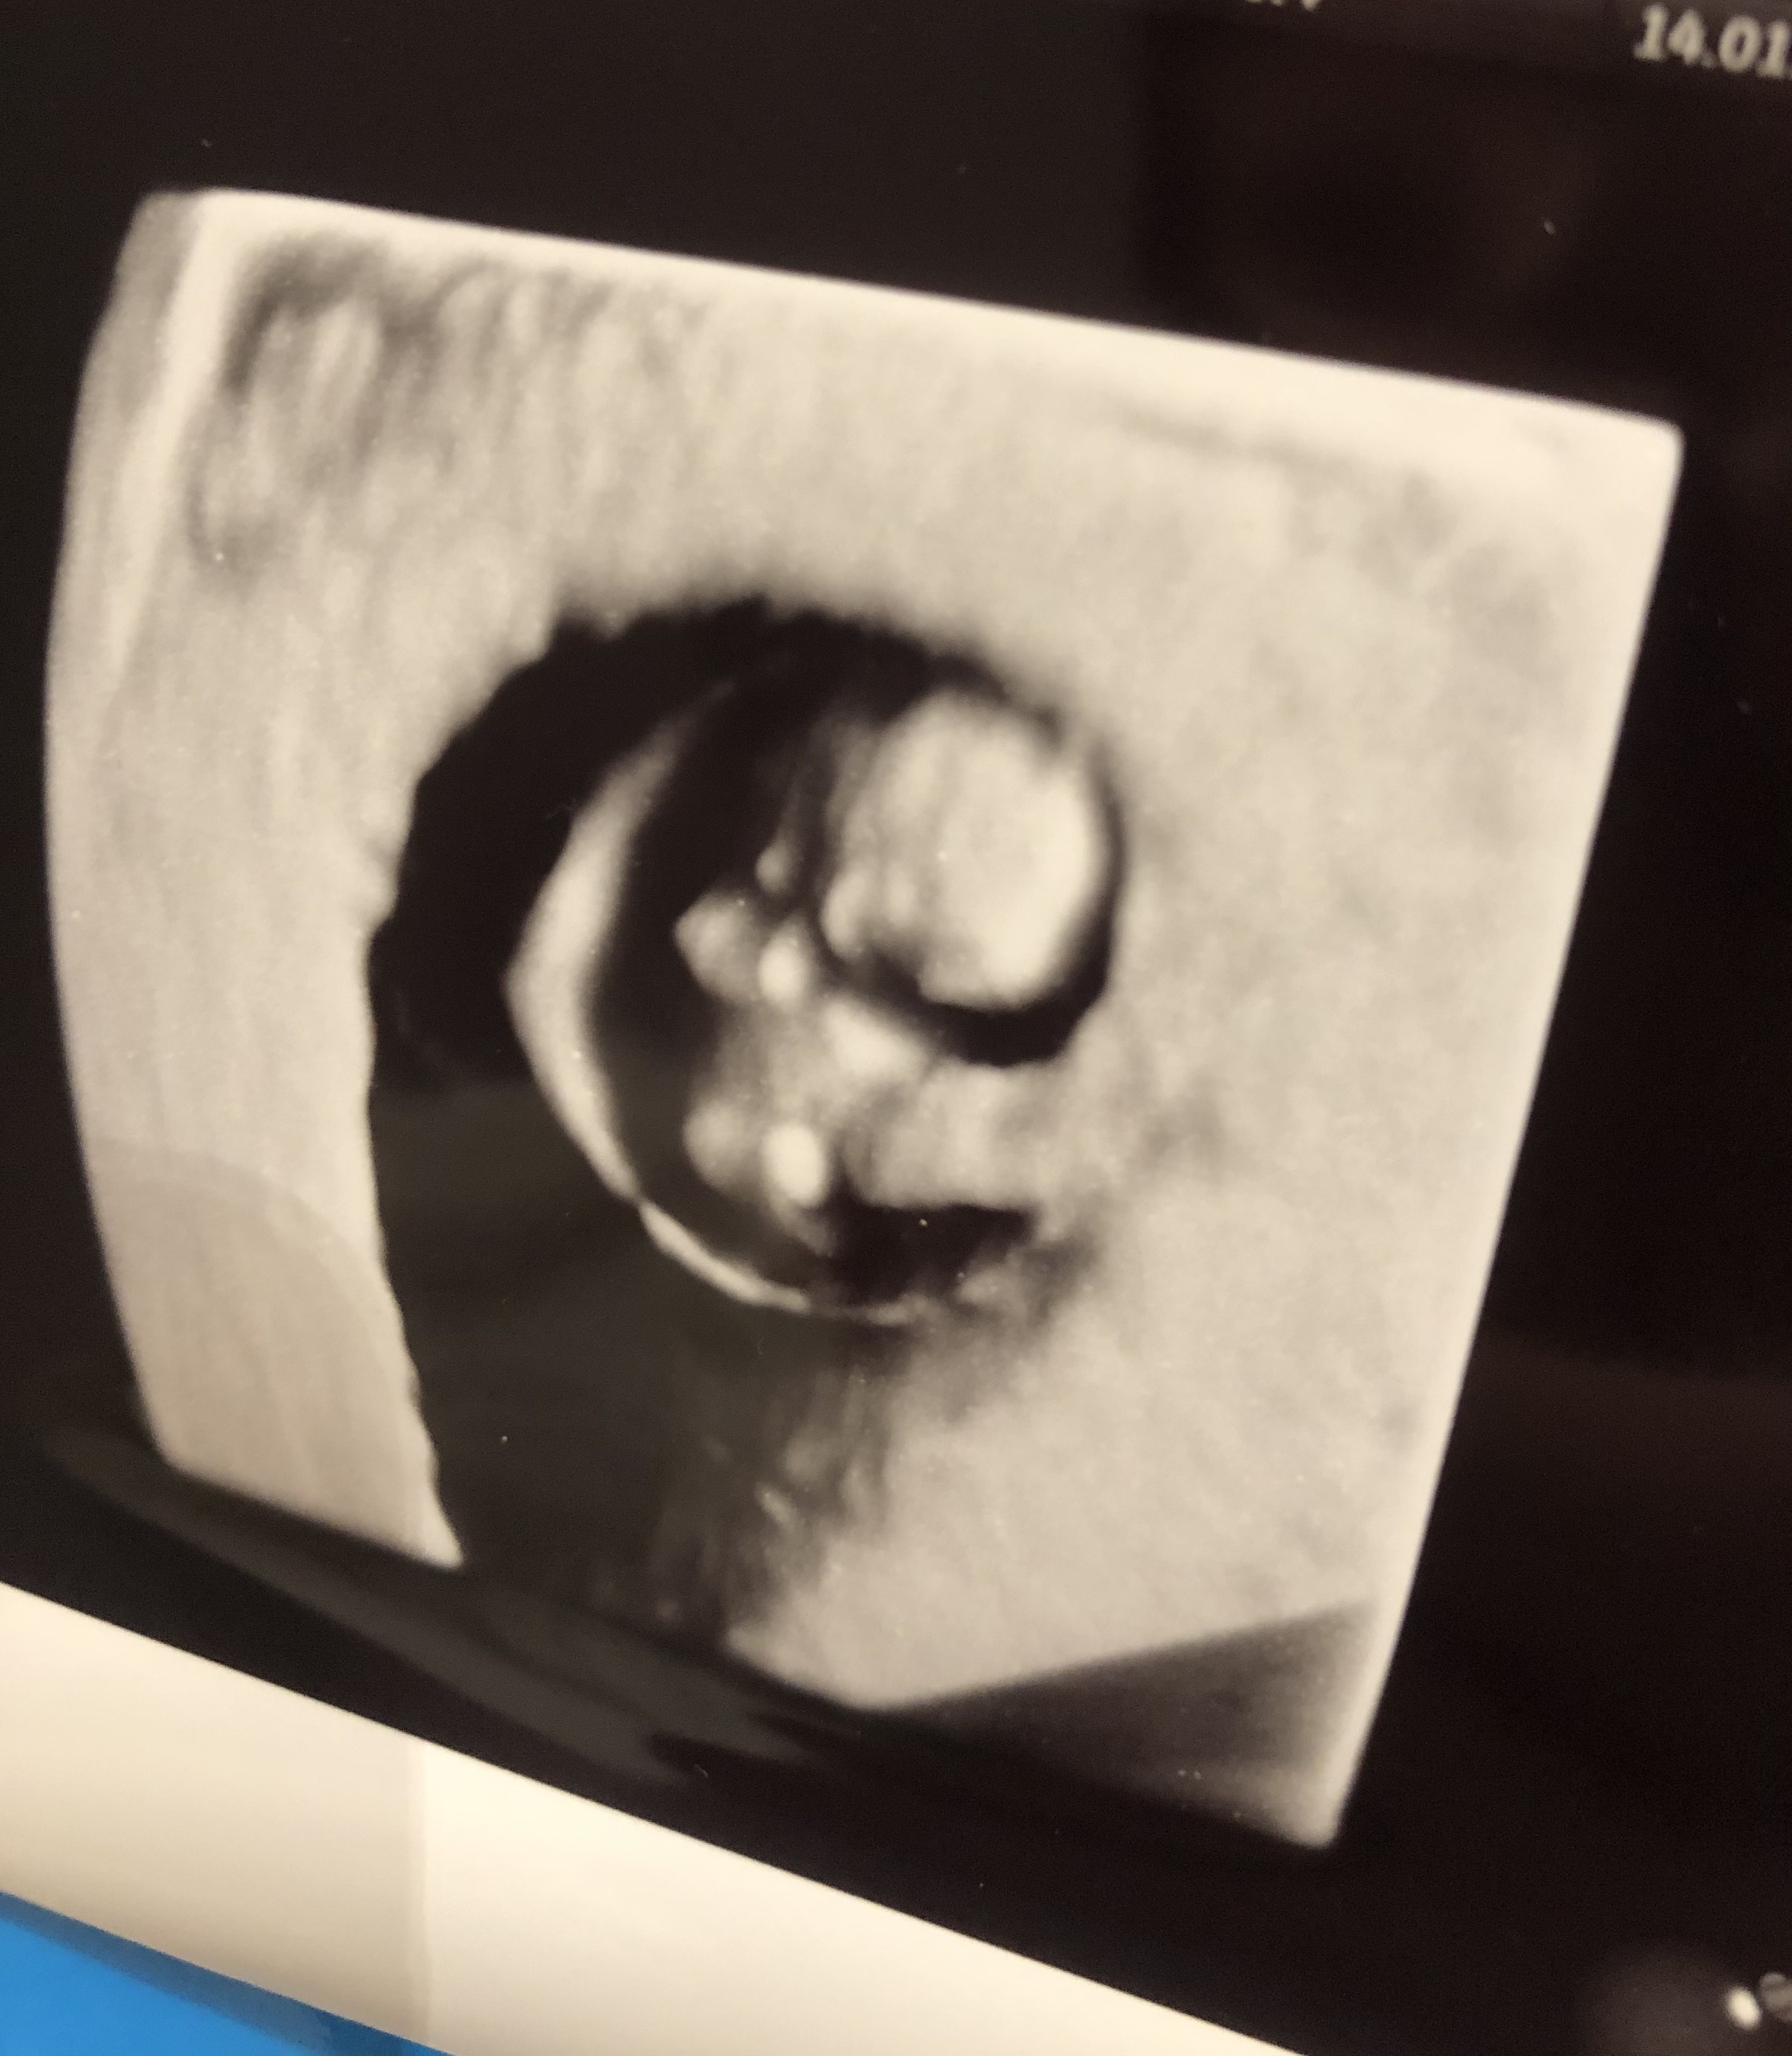

Dziewczynki, słyszałam serduszko. Moja faosolka/mój fasolek wyglada tak jak zdjęciu💕💕 kamień z serca, radość i łzy❤️

Załączniki

• 07E82203-0B6D-42D4-BBF1-FFAB4124C532.jpeg

07E82203-0B6D-42D4-BBF1-FFAB4124C532.jpeg

1,2 MB · Wyświetleń: 151